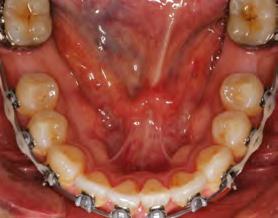

52 | SONRIENDO AL FUTURO

Tratamiento ortodóncico en paciente adulto tratado con extracciones de primeros molares permanentes. Reporte de caso

en paciente adulto tratado con extracciones de primeros molares permanentes. Reporte de caso

Dentista y Paciente 52 Sonriendo al futuro